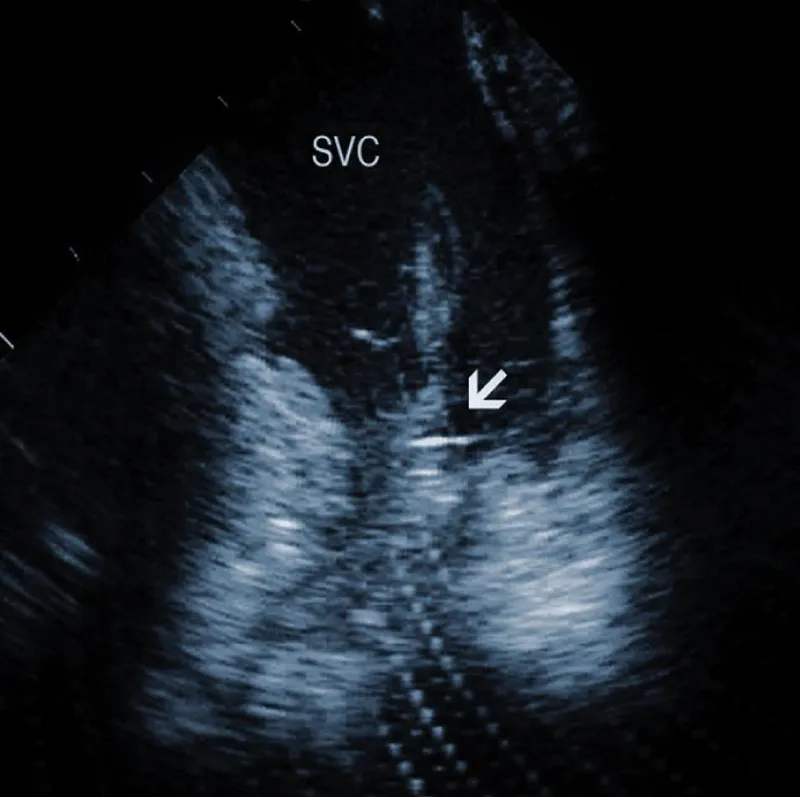

Areas of fibrous adherence: Areas of fibrous adherences or attachments (i.e., scar tissue) can be visualized as echo-dense structures along the lead course (Figure 3A). Multiple leads are usually attached by fibrous tissue together (Figure 3B). The location of fibrous adherence can be anywhere in the course of the lead [7,10]. In a study by Bongiorni, et al. [7], scar tissue was noted by ICE in the subclavian vein, innominate vein, and the right ventricle in about 80%, 68%, and 68% of cases, respectively. Sadek, et al. [10] described attachments less frequently – only in 18/50 pts (36%), predominantly intracardiac. Anecdotal cases were reported on specific locations of adhesions, such as a vulnerable “stalk” attaching the papillary muscle to the RV endocardium [18]. Notably, the fibrous attachment presence correlated with the extraction procedure’s difficulty. These patients were more likely to have a “complex” extraction procedure. Subjects who did not have evidence of lead attachment were less likely to require the advancement of the extraction sheaths past the superior vena cava and less likely to require advanced extraction tools such as snares.

Figure 3B: A convolute of 2 leads attached together with fibrous tissue at the level of tricuspid valve (arrows). RA: Right Atrium; RV: Right Ventricle.